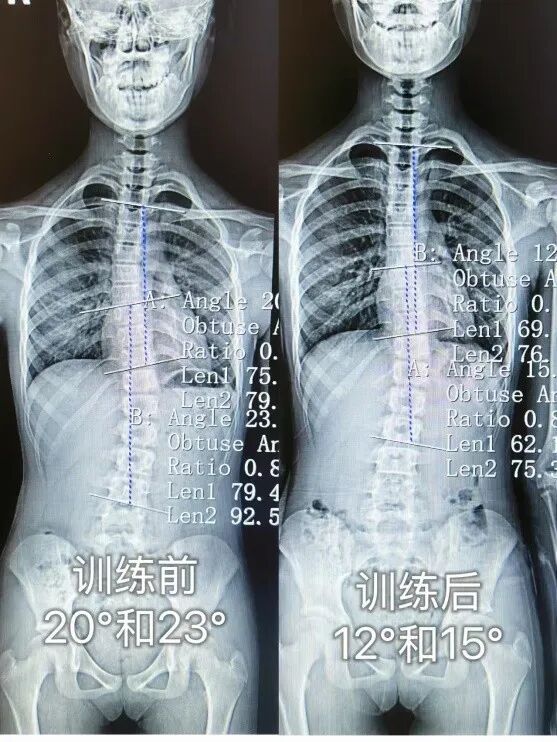

脊柱侧弯是脊柱的三维畸形,于冠状面、水平面、矢状面呈现异常弯曲与旋转,X 光 下 Cobb 角>10° 即可确诊。其病因繁杂,涵盖先天性、特发性、神经肌肉性、功能性等,其中特发性最为常见,约占 80%,且女性多发。